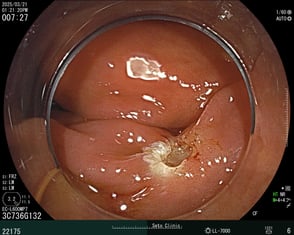

ワイヤーで切除して止血を確認した